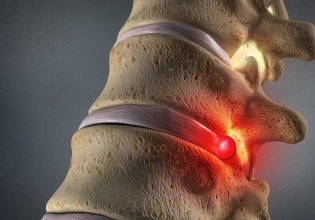

Spinal discs are soft, rubbery pads between the vertebrae that make up the spinal column. Each disc has a tough outer layer (annulus fibrosus) and a gel-like center (nucleus pulposus). A herniated disc occurs when the nucleus pulposus bulges out through a tear or rupture in the annulus fibrosus. This can press on the spinal nerves or the spinal cord, leading to symptoms.

Lower Back (Lumbar Herniation): Pain in the lower back, buttocks, thigh, and calf. Pain may radiate down the leg (sciatica).

Neck (Cervical Herniation): Pain in the neck, shoulder, arm, or hand. Pain may radiate down the arm.

Numbness or Tingling:A herniated disc can cause numbness or tingling in the areas served by the affected nerves.

Weakness: Muscles served by the affected nerves may weaken, leading to difficulty in lifting or holding objects.